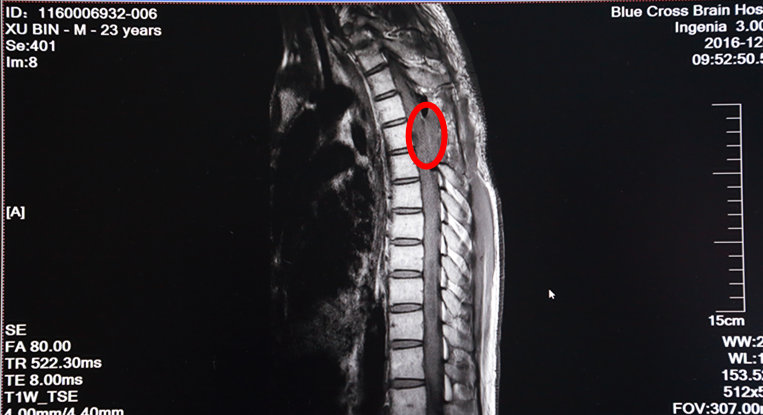

术后MRI增强扫描:红圈内肿瘤物已消失

次日,手术进行。术中,在全麻下打开硬脊膜,手术显微镜下,脊髓表面见大量迂曲的血管团,选择血管相对稀少而功能不是很重要的区域切开薄如薄纸的脊髓,小心沿肿瘤边缘分离并逐次切断供应肿瘤的血管,顺利地完成了肿瘤的全切除。术后增强MRI示肿瘤已经全部切除了。

目前病人的状况很好,双下肢痛觉触觉及右下肢深感觉已经恢复,左下肢肌力较术前好。据介绍:血管母细胞瘤切除术是精细度很高的手术,血管母细胞瘤本身就是血管组成,肿瘤与脊髓共用血管,肿瘤切除的同时,不能让脊髓血管受到损伤,再加上脊髓很嫩很薄,易造成横贯性脊髓损害,出现瘫痪、大小便失禁等不可逆损伤。患者徐某的手术是非常成功的,不仅肿瘤全切,更没有造成脊髓损伤,病人算是安全地度过了最凶险的一关,接下来将视患者身体情况,制定进一步手术方案,对脑部肿瘤进行切除。